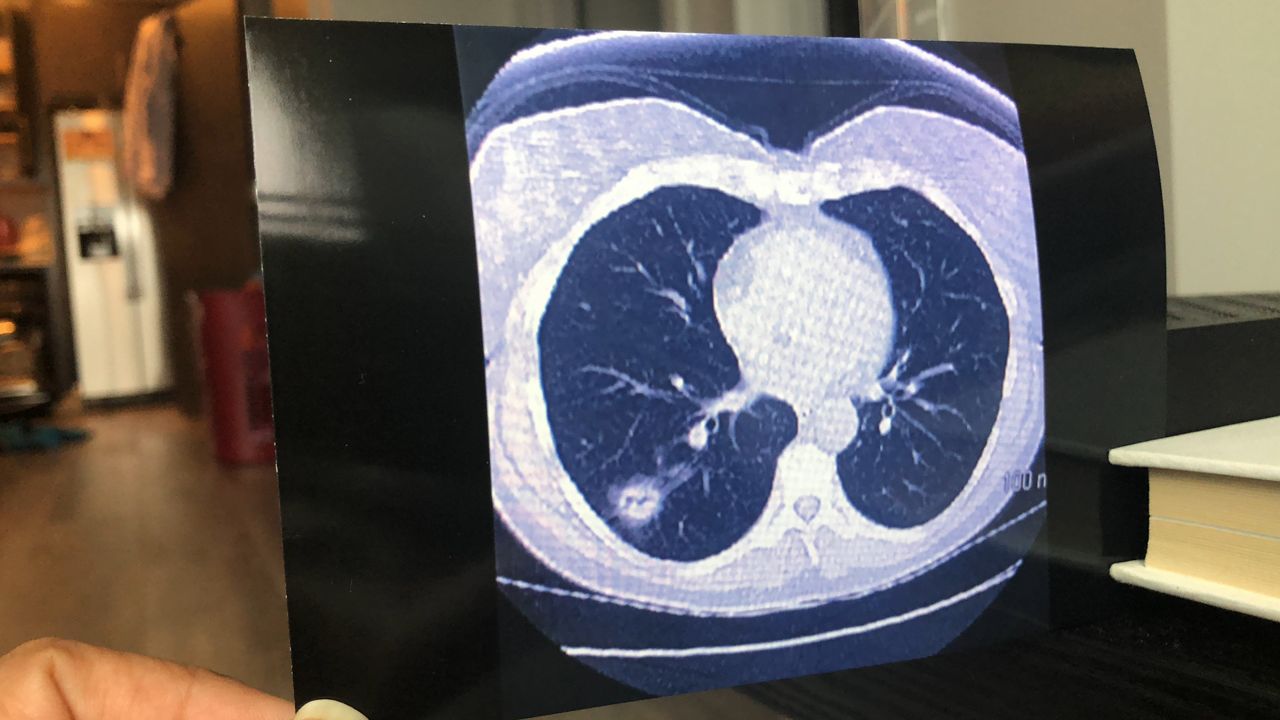

But catching signs of the disease early is key to survival.

“Lung cancer screening is key to early diagnosis, and early diagnosis saves lives. Unfortunately, here in New York, not enough people are getting this lifesaving screening,” said Trevor Summerfield, the director of advocacy at the American Lung Association in New York. “We all can help reduce the burden of lung cancer in New York. If you are eligible for lung cancer screening, we encourage you to speak with your doctor about it. If a loved one is eligible, please encourage them to get screened.”